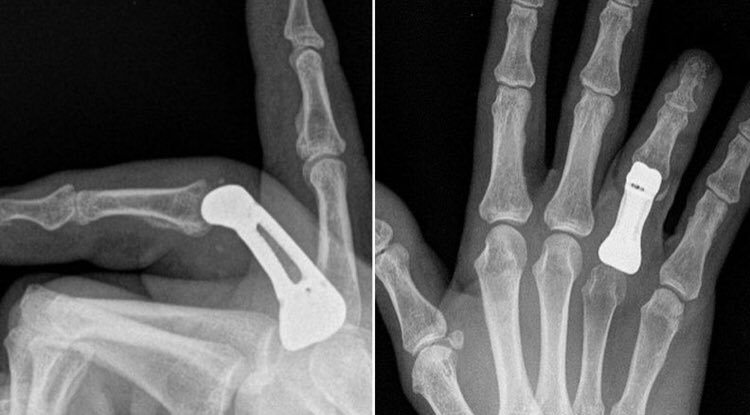

Ortopedi Doktoru در توییتر Orthopaedic Surgeons Replace Man S Fingerbone With A 3d Printed Part Https T Co Jlhdstchax Ortopedi De Onkoloji K Bir Vakada 3d Yazici Kullanimi Ile Ilgili Guzel Bir Vaka Ornegi Tip Orthopaedics